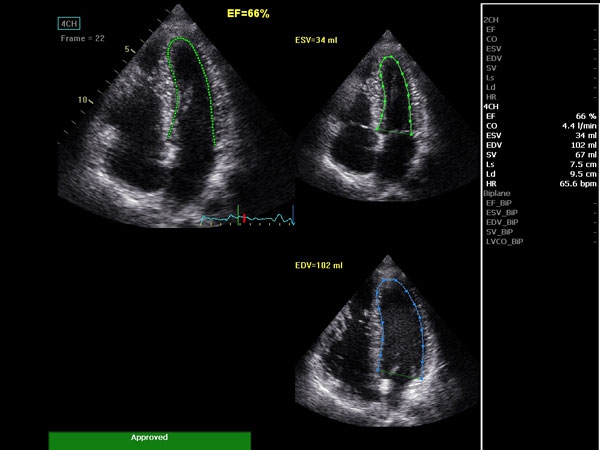

• AutoEF (Auto Ejection Fraction) — функция автоматической недоплеровской количественной оценки глобальной сократительной функции левого желудочка с выделением зоны интереса по технологии спекл-трекинга.

AUTO 2D EF:

Да